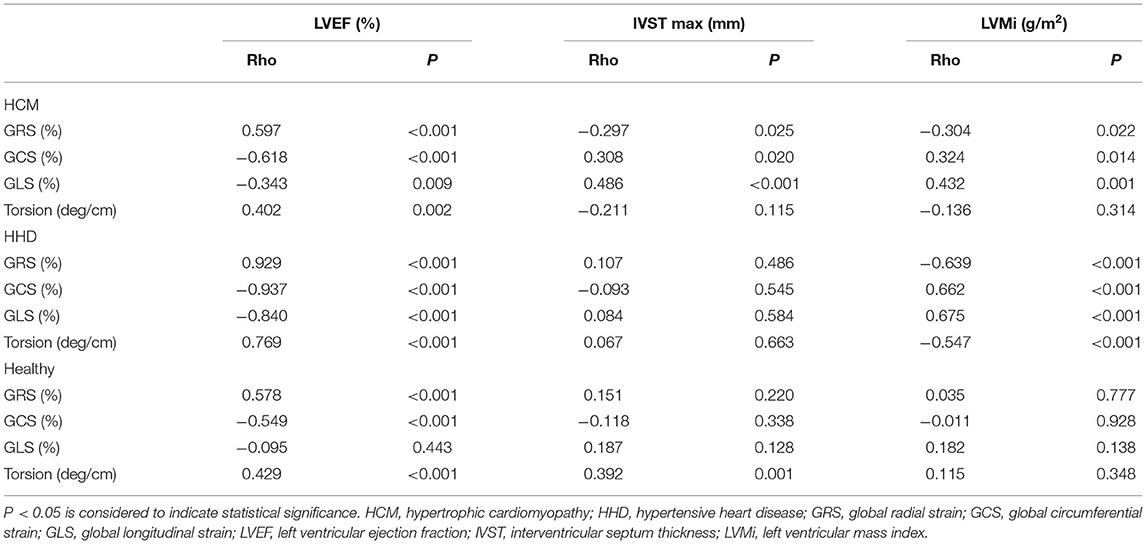

Correlations of Left Ventricular Strain With Functional and Structural Parameters

In patients with HCM, GRS, GCS, and GLS showed correlations with LVEF, IVST max, and LVMi (Table 3). Especially, GRS and GCS presented strong correlations with LVEF (GRS, R = 0.597, P < 0.001; GCS, R = −0.618, P < 0.001). In addition, torsion was mildly associated with LVEF (R = 0.402, P = 0.002) (Figure 3). In patients with HHD, GRS, GCS, GLS, and torsion were correlated with LVEF and LVMi (all P < 0.001). In the healthy group, GRS, GCS, and torsion were only associated with LVEF (all P < 0.001).